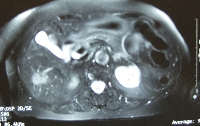

Πρόκειται για γυναίκα ασθενή 77 ετών η οποία, στα πλαίσια διενέργειας προγραμματισμένου προληπτικού απεικονιστικού ελέγχου με υπερηχογράφημα, διαπιστώθηκε ότι έφερε μονήρη ηπατική βλάβη μεγέθους 3.5 cm μεταξύ του 5ου και 6ου ηπατικού τμήματος (εικόνα 1). Η διαδερμική βιοψία ανέδειξε χολαγγειοκαρκίνωμα. Σε σχετικό έλεγχο δεν ανιχνεύθηκαν εξωηπατικές μεταστάσεις. Η ασθενής υποβλήθηκε σε ερευνητική λαπαροτομία, διεγχειρητικό υπερηχογράφημα (αρνητικό για άλλες, πλην της ήδη γνωστής, βλάβες) και τελικά σε ηπατεκτομή των τμημάτων 5 και 6 με συνοδό χολοκυστεκτομή (εικόνες 2, 3 και 4). Έλαβε εξιτήριο την 6η μετεγχειρητική ημέρα.